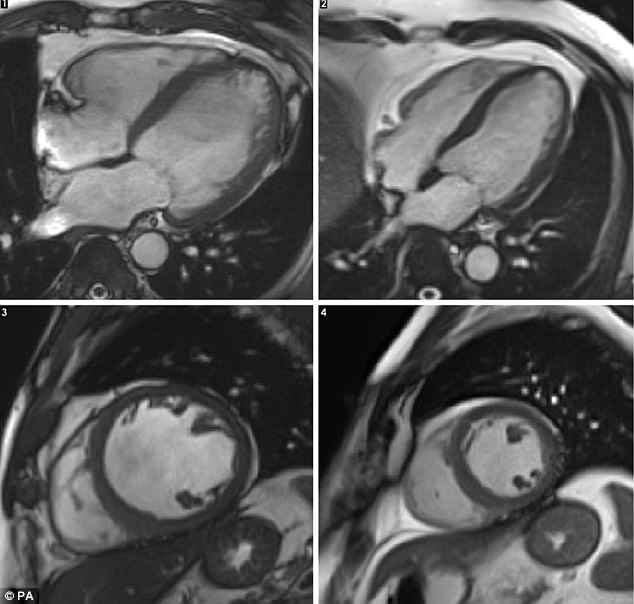

Un estudio reveló imágenes que muestran la diferencia entre un corazón sano y un corazón de un bebedor asiduo, las cuales detallan que las personas que consumen alcohol constantemente tienen dicho órgano más grande, lo cual afecta su capacidad de bombear sangre alrededor del cuerpo, debido a un gen defectuoso.

El DCM ocurre cuando los tejidos del corazón se estiran y adelgazan, afectando la capacidad del órgano para bombear sangre.